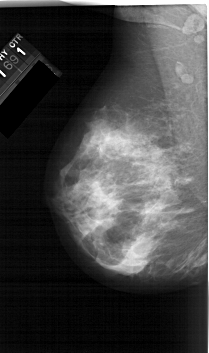

A_1566_1.RIGHT_MLO

RIGHT_MLO LINES 6406 PIXELS_PER_LINE 3361 BITS_PER_PIXEL 12 RESOLUTION 43.5 OVERLAY